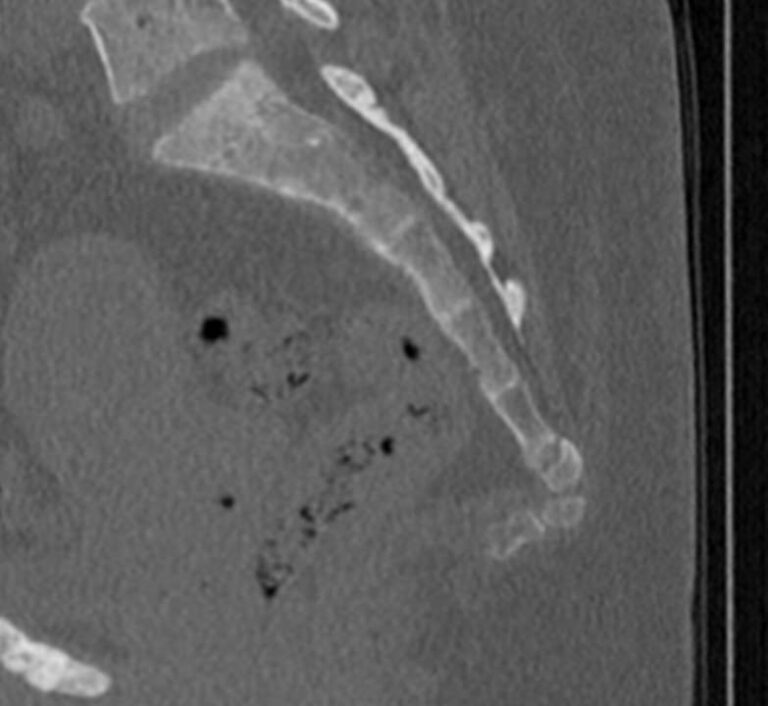

- травматические повреждения позвоночника (компрессионные и оскольчатые переломы);

- патологические изгибы позвоночника, сколиоз, усиленный или выпрямленный лордоз как нарушение статической функции позвоночника;